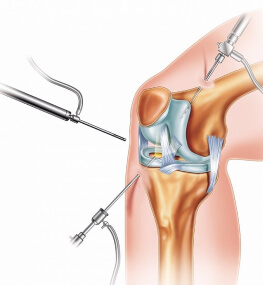

Крім операції під назвою - ендопротезування кульшового суглоба, ціна на яку цілком доступна у нас, досить-таки часто в госпіталі проводиться і заміна колінного суглоба (ціна залежить від типу операції). Заміна суглоба в коліні - одна з найбільш затребуваних операцій.

Ендопротезування колінного суглоба в залежності від того який ступінь пошкодження тканин, може бути тотальною або частковою.

Операція по заміні суглоба є абсолютно безпечною. При цій процедурі використовується високоякісний протез, який підбирається індивідуально під кожного пацієнта.

Операція, яка позбавляє від постійного болю - заміна суглоба (ціна залежить від місця локалізації та типу операції) поверне людину до колишнього життя, адже виконується за допомогою нових технологій, що гарантують швидке одужання.